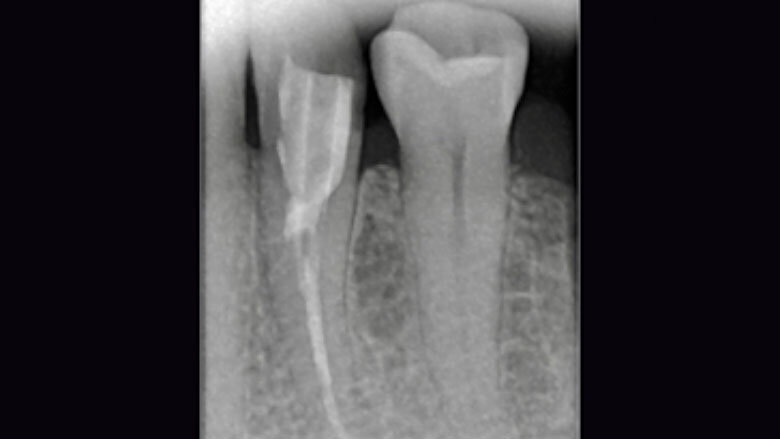

Fig. 1. Situación inicial: el diente 34 estaba fuertemente dañado. La encía se había adentrado en la cavidad.

Una paciente de 48 años acudió a la clínica porque el diente 34 se le había fracturado y otro odontólogo le había sido previamente que no se podía salvar. Durante el examen clínico se observó un defecto distooral muy extendido. La encía se había adentrado en la cavidad. La radiografía reveló una obturación insuficiente del canal radicular. Dado que una preparación de corona completa habría provocado una pérdida de las zonas de pared vestibulares y mesiales del diente, se decidió realizar una endocorona con VITABLOCS Mark II. Tras la gingivectomía, se reconstruyó el diente 34 con composite mediante láser y se llevó a cabo un tratamiento de revisión.